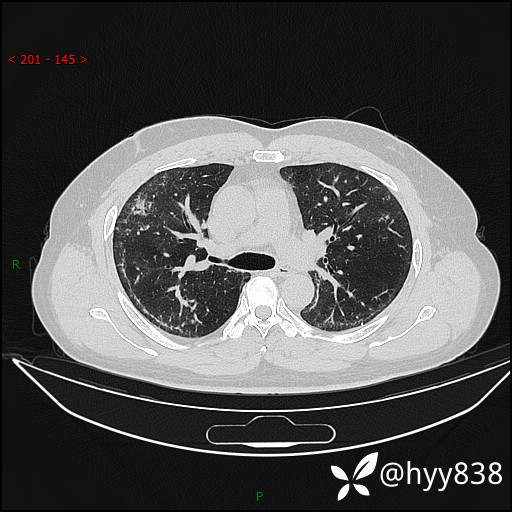

辅助检查:CT

临床诊断:间质性肺炎

第一次胸部CT